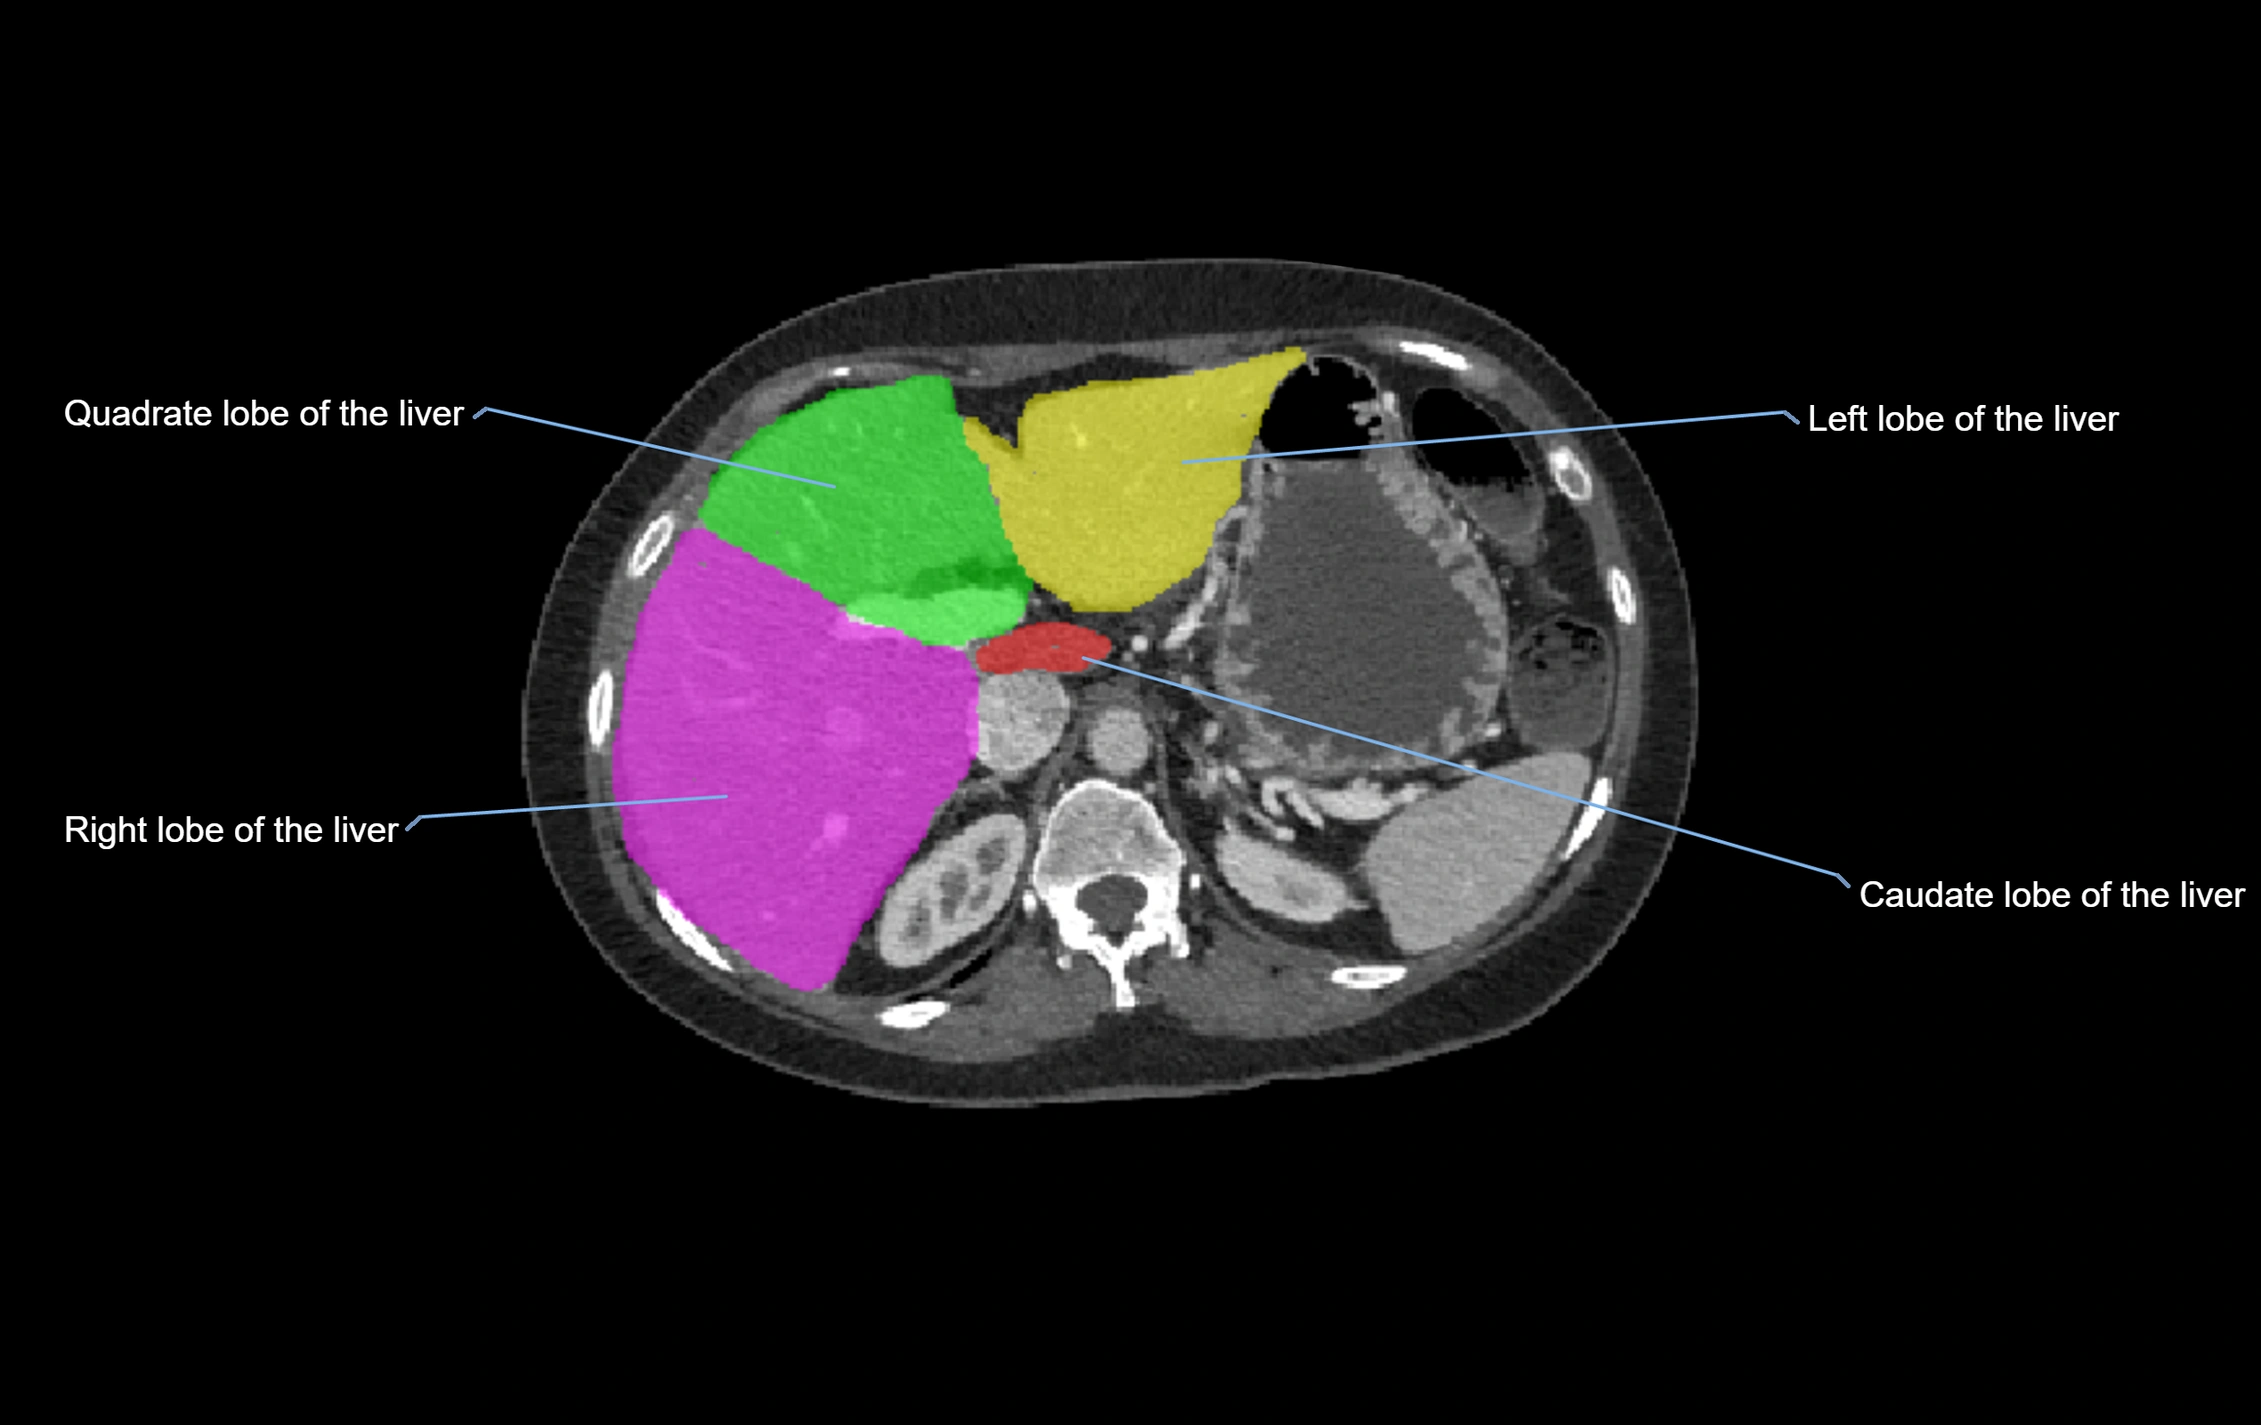

CT Image

image